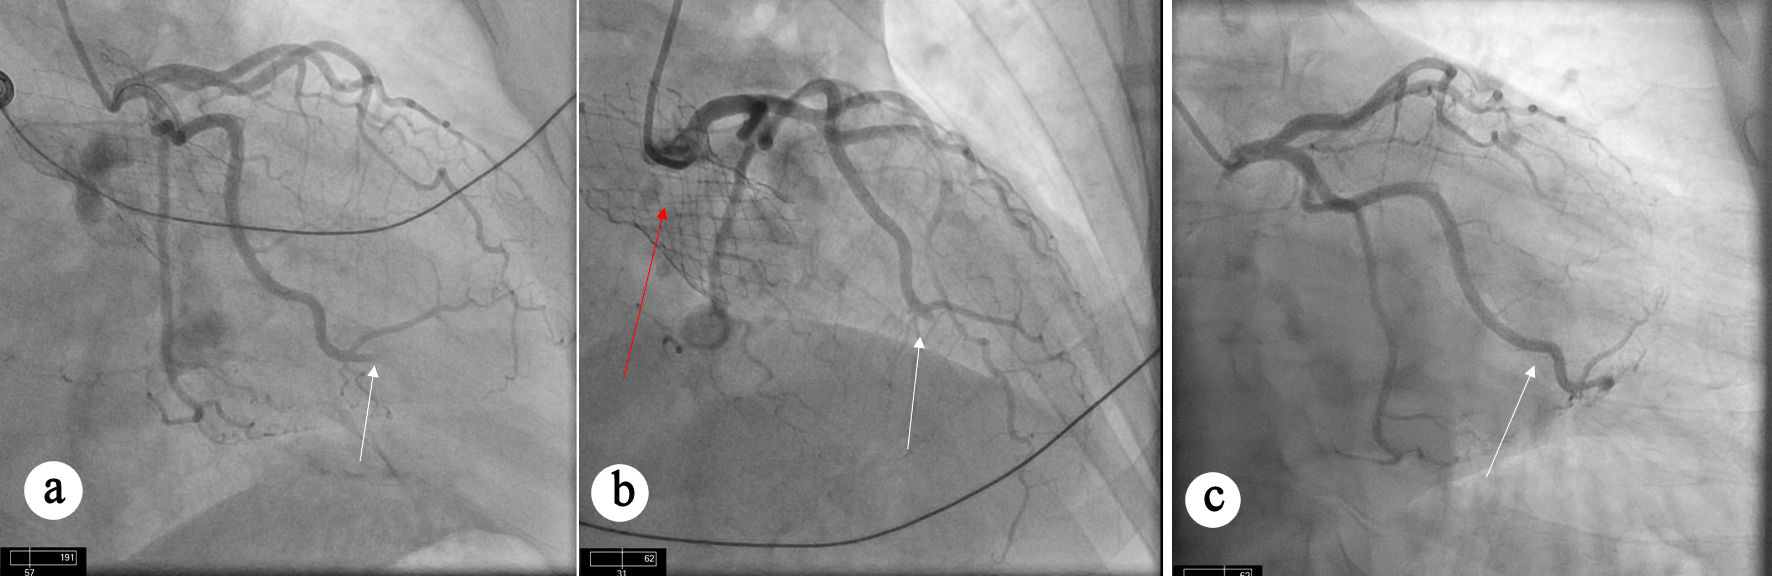

Fifty months after TAVR, he presented with anterolateral STEMI. Notably, the pre-TAVR coronary angiogram demonstrated normal coronary arteries without evidence of obstructive coronary artery disease (CAD) (Fig. 1a); however, repeat left heart catheterization at the time of presentation with STEMI revealed abrupt 100% occlusion of the left anterior descending artery (Fig. 1b), diagonal branch (Fig. 1b), and obtuse marginal (OM) branch (Fig. 1c), consistent with an embolic pattern. Aspiration thrombectomy restored TIMI 3 flow in all the affected vessels (Fig. 1d, e).

Figure 1. Angiographic views showing coronary arteries. (a) Diagnostic angiogram before TAVR procedure showing angiographically normal coronary arteries without any evidence of obstructive CAD. (b) Occlusion of LAD and diagonal branch artery. (c) Occlusion of OM artery. (d, e) Restoration of flow can be seen in LAD (white arrow), diagonal branch (red arrow), and OM artery (blue arrow) after aspiration thrombectomy. CAD: coronary artery disease; LAD: left anterior descending; OM: obtuse marginal; TAVR: transcatheter aortic valve replacement.